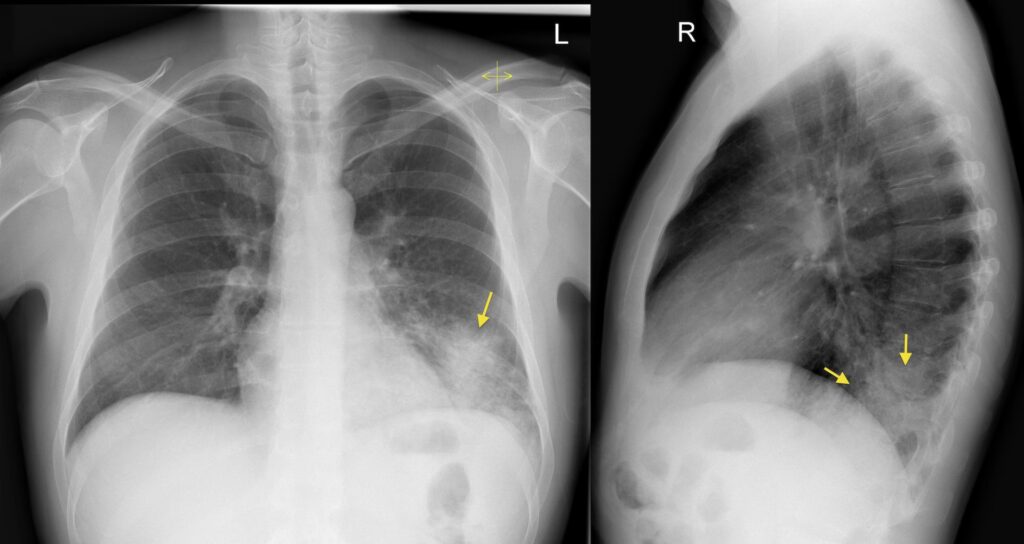

På et normalt røntgenbillede fremstår lungerne som mørke, fordi de primært er fyldt med luft, som strålerne let passerer igennem. Knogler og hjertet fremstår hvide, da de er tættere og absorberer mere stråling. Når der er lungebetændelse, vil de betændte områder i lungen, der er fyldt med væske og pus, også fremstå som hvidlige eller uklare pletter. Disse områder kaldes infiltrater eller konsolideringer. Et røntgenbillede kan hjælpe lægen med at:

- Bekræfte diagnosen: Visualisere tilstedeværelsen af infiltrater, der er et klassisk tegn på lungebetændelse.

- Bestemme omfanget: Vise, hvor stor en del af lungen der er påvirket, og om det er i den ene eller begge lunger.

- Identificere komplikationer: Opdage eventuelle komplikationer som væskeansamling omkring lungen (pleural effusion) eller dannelsen af en byld (absces).

Ikke alle lungebetændelser ser ens ud. En "typisk" bakteriel lungebetændelse viser sig ofte som en velafgrænset fortætning i en enkelt lungelap (lobar pneumoni). En "atypisk" lungebetændelse, ofte forårsaget af vira eller Mycoplasma-bakterien, kan give mere diffuse og spredte forandringer, der kan være sværere at identificere.